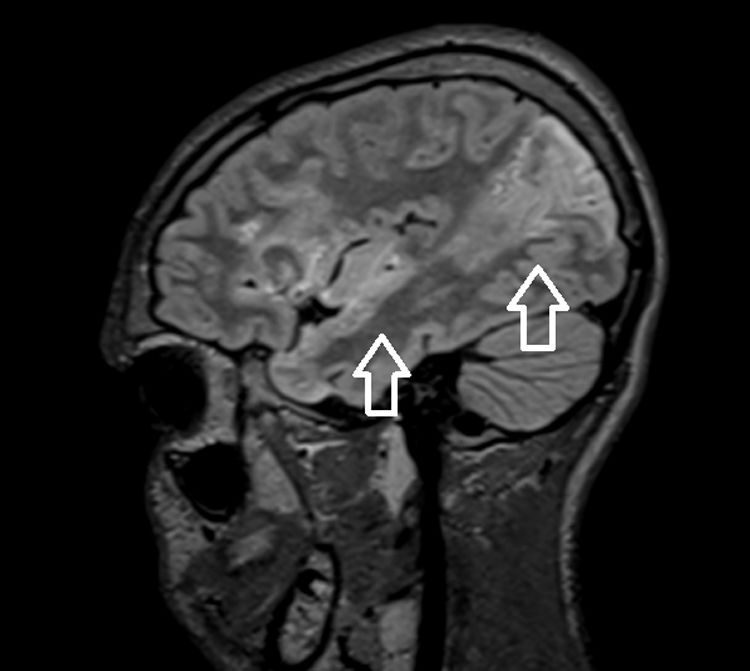

Las evaluaciones iniciales, incluyendo analítica, toxicología, TAC craneal y punción lumbar, fueron anodinas. A continuación, desarrolló hemiparesia derecha con hemianopsia homónima y afasia (puntuación de 9 en la escala PedNIHSS). La angio-TC cerebral mostró un accidente cerebrovascular embólico secundario a la oclusión del segmento insular de la arteria cerebral media. La evaluación etiológica reveló una masa de gran tamaño en la aurícula izquierda (fig. 1) tratada mediante escisión quirúrgica, con confirmación del diagnóstico de mixoma por histopatología.